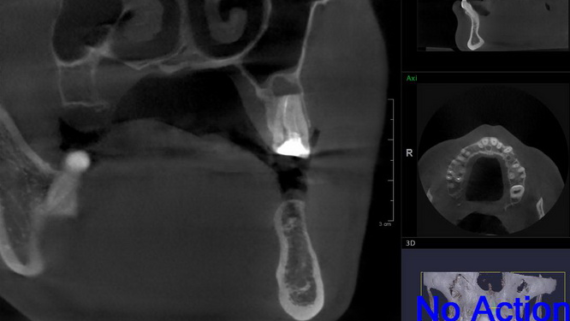

сделано в CLINIC IN: РЕСТАВРАЦИЯ РЕЗЦОВ ВЕРХНЕЙ ЧЕЛЮСТИ